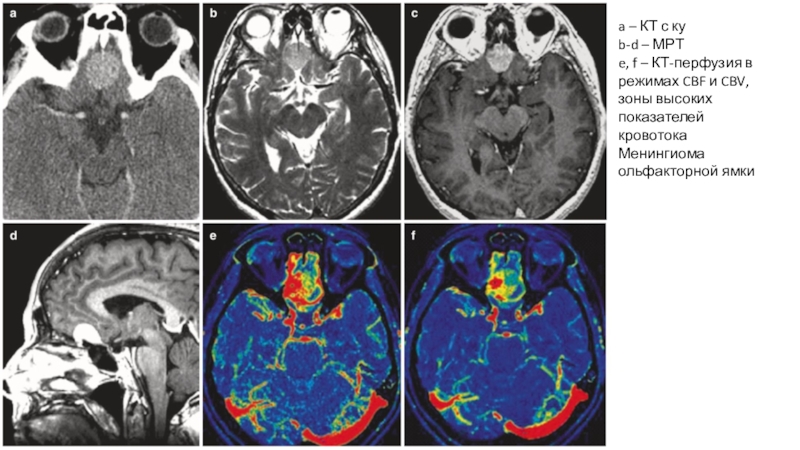

Слайд 31a – КТ с ку

b-d – МРТ

e, f – КТ-перфузия

в режимах CBF и CBV, зоны высоких показателей кровотока

Менингиома

ольфакторной ямки

a – КТ с куb-d – МРТe, f – КТ-перфузия в режимах CBF и CBV, зоны высоких